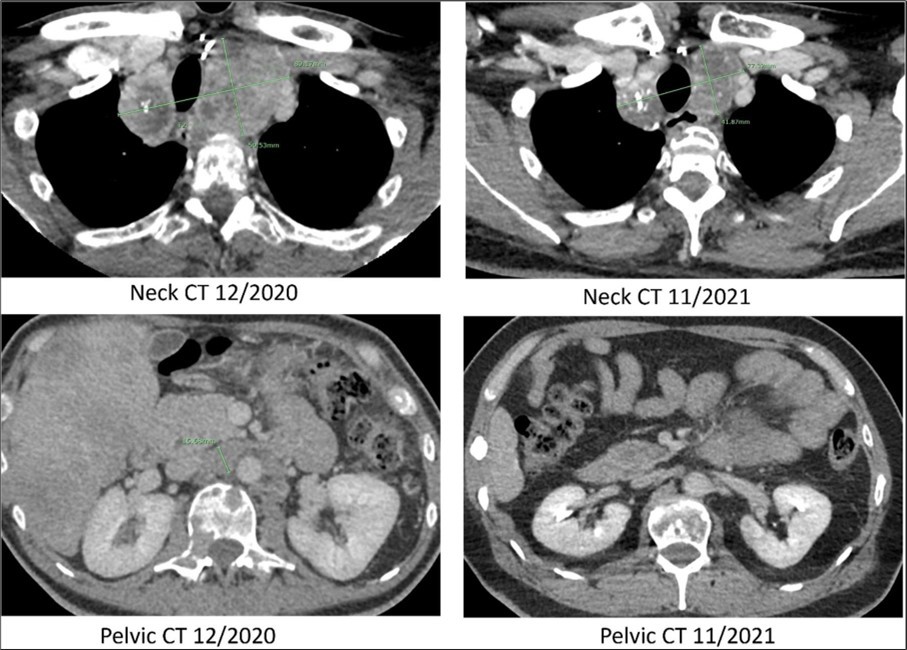

The patient presented to radiation oncology in September 2020 with severe back pain and shown to have widely metastatic disease with a calcitonin level >40,000 pg/mL and carcinoembryonic antigen (CEA) level >2,500 ng/mL. Computerized tomography (CT) with contrast of the chest, abdomen and pelvis revealed worsening mediastinal lymphadenopathy with progressive mass effect and rightward deviation of the trachea at the superior mediastinum (Figure 2). Patient received radiotherapy for four weeks causing epiglottitis and subsequent 25lb weight loss. Progressive osseous metastatic disease was identified with innumerable new expansile lytic lesions throughout the vertebral bodies, posterior elements, ribs, sternum, and scapulae, resulting in pathologic fractures of the C7, T4, T6, and T12 vertebral bodies as well as right posterior 10th rib. In addition, there were innumerable new and enlarging liver lesions and bilateral pulmonary nodules. Patient declined further therapy including further imaging studies.

Figure 2.Computed tomography. CT scans of the neck and pelvis with contrast in December of 2020 (prior to Pralsetinib) and in November of 2021 (eleven months after the start of Pralsetinib). The 2020 neck CT showed a large mass at the thoracic inlet measuring 89mm x 50mm. In 2021 this same mass post treatment had decreased in size to 77mm x 41mm. The 2020 pelvic CT showed a retroperitoneal lymph node enlargement to 15mm, which resolved on the 2021 scan.